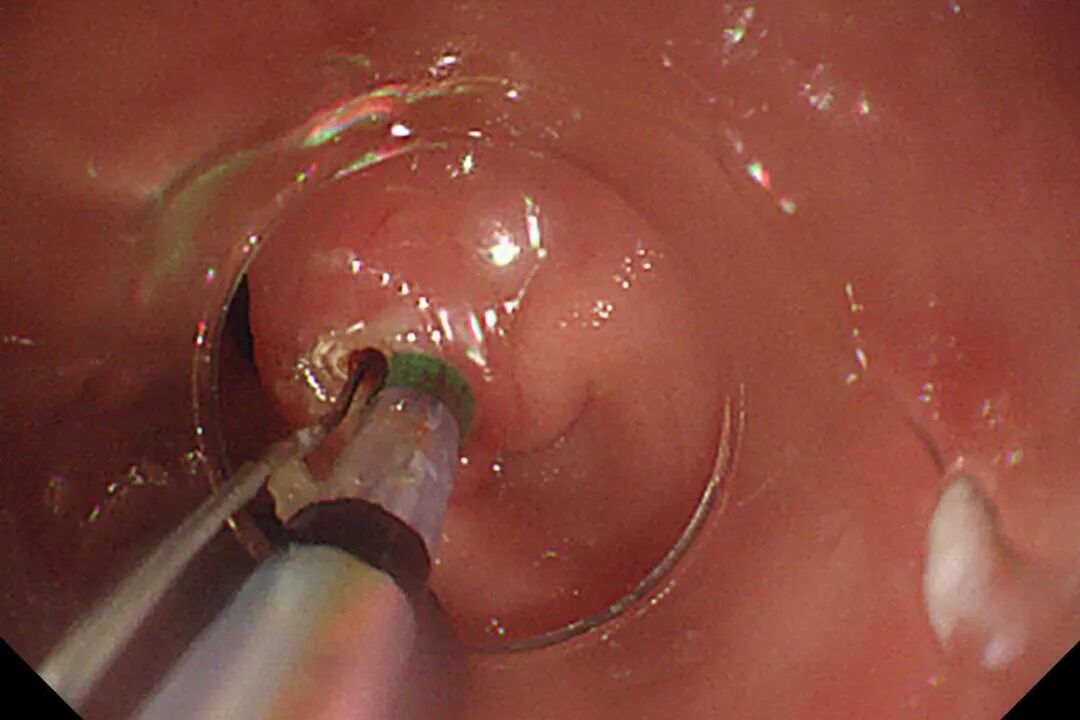

B-II式术后胃-输入袢

术中胃镜戴透明粘膜吸套进镜,可见胃、十二指肠、空肠呈B-II式术后改变,吻合口发红。经团队仔细查找,于输入袢找到十二指肠大乳头,插入三腔括约肌切开刀,并顺利将导丝送入胆总管。造影验证,可见胆总管明显扩张,直径最宽处约16mm,中段见一长条形结石影,约13x12mm。切开乳头后,扩张乳头括约肌及胆总管括约肌,用特制取石导管及取石网篮取出大量黄色块状结石及碎渣样结石。术后置入鼻胆引流管引流,顺利结束手术